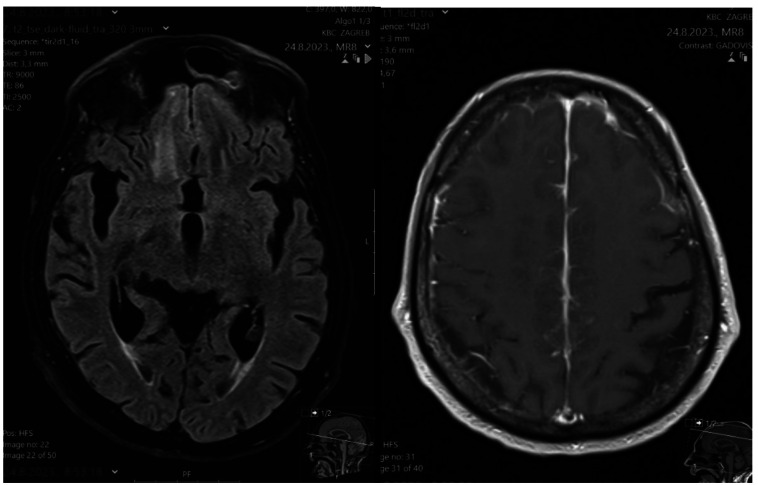

Prolonged cocaine inhalation can cause destruction of nasal mucosa and ethmoid sinuses and palate perforation, thus inducing cocaine-induced midline destructive lesions (CIMDL) that affect only a limited number of predisposed patients. CIMDL are an autoimmune necrotizing inflammatory phenomenon associated with the presence of atypical antineutrophil cytoplasmic antibody (ANCA). Patients complain of epistaxis, nasal obstruction, hyposmia, sinus infections, and facial pain. Protocol for the CIMDL diagnosis includes medical history, clinical examination, magnetic resonance imaging, laboratory tests, immunology and serology tests, and chest x-ray. A 68-year-old man presented with a brain extension mimicking an ischemic-like lesion with surrounding edema. A diagnosis of CIMDL was made in the light of the patient's medical history, imaging studies, and laboratory testing including pANCA positivity which seems to promote disease phenotype.